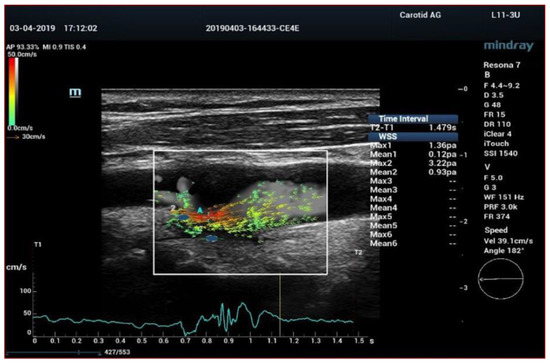

- Qiu, Y.; Dong, Y.; Mao, F.; Zhang, Q.; Yang, D.; Chen, K.; Shi, S.; Zuo, D.; Tian, X.; Yu, L.; et al. High-Frame Rate Vector Flow Imaging Technique: Initial Application in Evaluating the Hemodynamic Changes of Carotid Stenosis Caused by Atherosclerosis. Front. Cardiovasc. Med. 2021, 8, 617391. [Google Scholar] [CrossRef] [PubMed]

- Yiu, B.Y.; Lai, S.S.; Yu, A.C. Vector projectile imaging: Time-resolved dynamic visualization of complex flow patterns. Ultrasound Med. Biol. 2014, 40, 2295–2309. [Google Scholar] [CrossRef]

- Zhang, X.; Yao, Z.Q.; Karuna, T.; He, X.Y.; Wang, X.M.; Li, X.F.; Liu, W.C.; Li, R.; Guo, S.Q.; Chen, Y.C.; et al. The role of wall shear stress in the parent artery as an independent variable in the formation status of anterior communicating artery aneurysms. Eur. Radiol. 2019, 29, 689–698. [Google Scholar] [CrossRef]